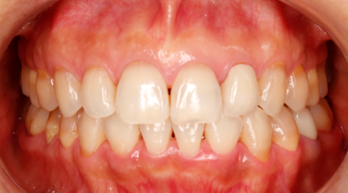

患者様は50代前半の女性で、「くいしばりが気になる」「顔が傾いている」「特に右顎が疲れる」というお悩みを抱えていました。

上の写真のように、治療開始前は「まっすぐ正面を見てください」と言っても、どうしても顔が曲がってしまう状態でした。また、「咬合平面」と呼ばれる上の歯並びのラインが、正面から見ると右下がりになっていました。

一見すると、下の前歯に多少の凸凹があるものの、そんなに目立って歯並びが悪いわけではないので、患者様も噛み合わせに問題があるとは思っていませんでした。

治療後の写真は、以下のとおりです。

噛み合っている面に傾きがなく、床に対して真っすぐになりました。また、「真っすぐ正面を見てください」と伝えたときに、首が曲がらなくなりました。3Dデータを見ても、接触点(緑色と赤色)が全体に分散しました。

患者様いわく、不均衡な筋肉の緊張が取れて、食いしばりも気にならなくなったとのこと。余計な力がかからないので、顎が疲れることもなくなったそうです。顔の傾きは顕著に改善していますね。